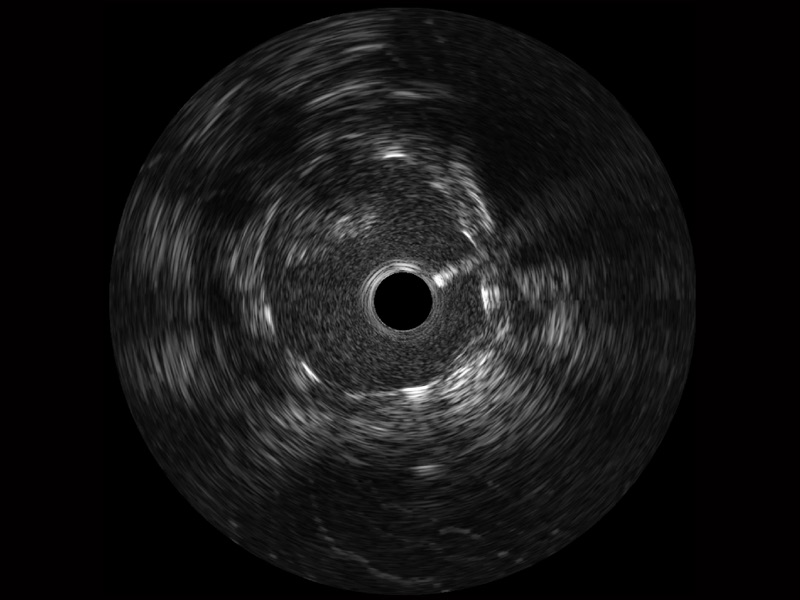

传统IVUS图像

对比传统IVUS导管成像,竞技宝(JJB)官方网站宽频IVUS图像的近场支架梁显影更细腻,远场中膜外血管仍清晰可辨,兼顾远中近,兼顾分辨力与穿透深度